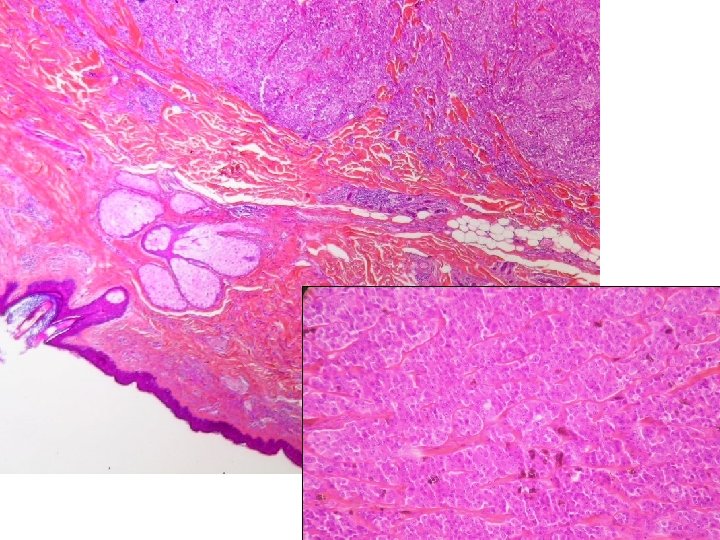

Surcharges endogènes pseudo tumorales ex : accumulation de cholestérol

Xanthome cutané